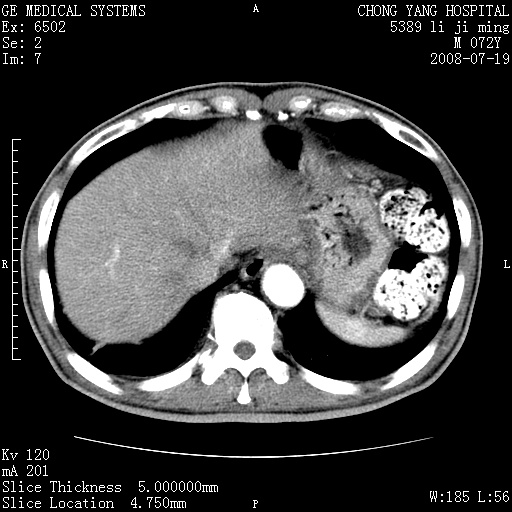

以下是引用zjzjr在2008-7-19 20:57:00的发言:[br]胰头增大,边缘模糊,周围可见渗出影,右侧肾前筋膜增厚.支持胰腺炎.

以下是引用不学无术在2008-7-19 23:15:00的发言:[br]胰腺增大尤以胰头明显,边缘模糊,周围可见渗出影,右侧肾前筋膜增厚,肠管於涨.支持胰腺炎